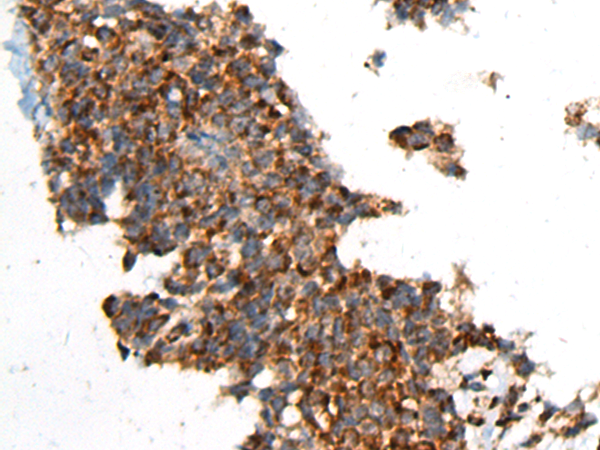

分类: 科研抗体货号: P01483别名: LAD; CD18; MF17; MFI7; LCAMB; LFA-1; MAC-1应用: IHC反应种属: Human, Mouse